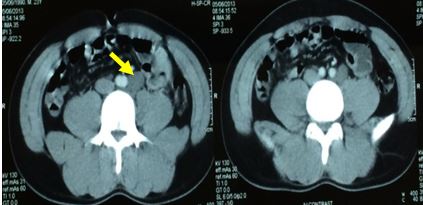

CT scan ngực, bụng 5/6/2013

Tầng ngực: Không có hạch trung thất

Tầng bụng: hạch cạnh trái động mạch chủ bụng kích thước 2-3 cm

Lách không to, không có dịch màng phổi, ổ bụng.

Hình ảnh hạch cạnh động mạch chủ bụng, kích thước 2-3cm.

Hình ảnh chụp CT ngực không phát hiện hạch trung thất.